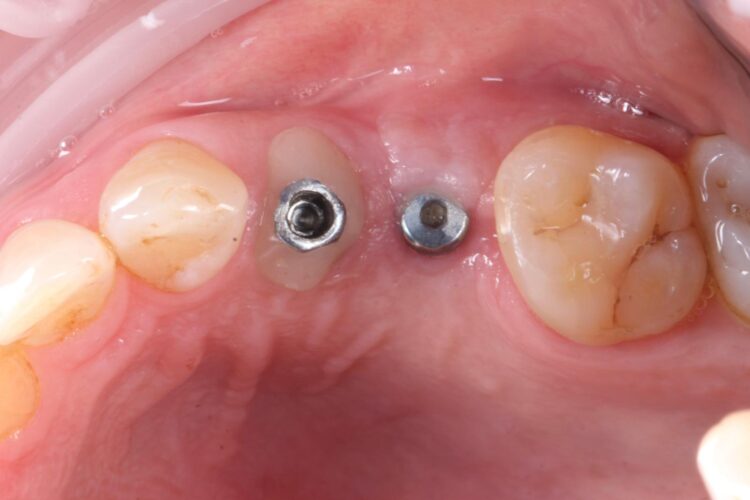

Consequently, the bone was contour-augmented, using MinerOss® Blend (BioHorizons Camlog), which provides a good combination of cortical and cancellous bone for efficient bone turnover and also maintains graft stability in the healing phase. The graft was held in place with a collagen membrane stabilised using resorbable sutures. The custom healing abutment is then placed and torqued (10Ncm) into the UL4 implant before the wound is approximated and sutured using a non-resorbable 6-0 Prolene suture.

An x-ray was taken immediately post-operatively to confirm that the temporary cylinder was seated correctly and wasn’t catching on the socket walls. This image also provided a reference for the custom healing abutment position and ensured that the bone graft material added to the jump gaps wasn’t preventing this abutment from fully seating.

The implant in the UL5 was uncovered 3 months later to reveal healthy tissues. Three weeks later the final scan was taken (using trios intra-oral scanner) for the fabrication of the definitive crowns. On the day of crown fits both abutments were removed and the crowns seated. Due to the UL4 site having a custom healing abutment, which had been supporting our ideal emergence profile, it was much easier to engage this restoration and seat within the already moulded soft tissues.